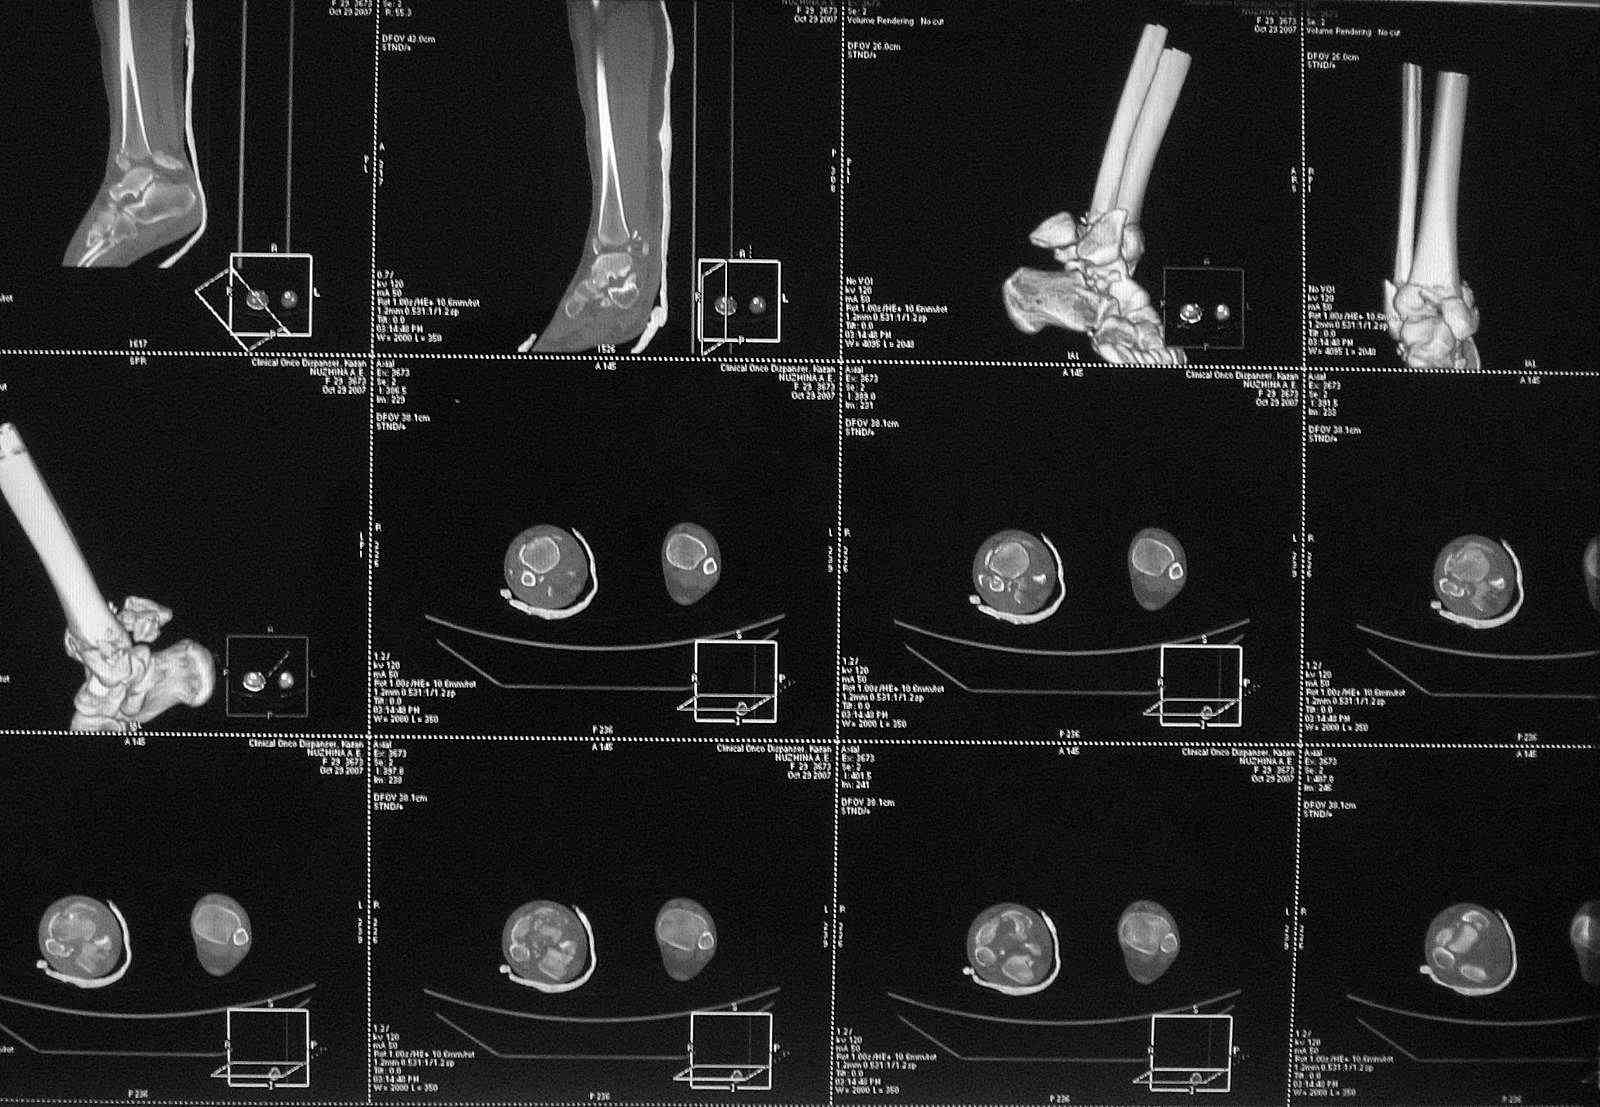

Re: Перелом пилона

Добавлены КТ снимки. Прошу прощения за качество.